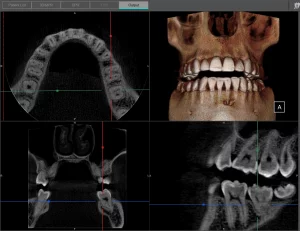

I wanted to share a unique case we’ve had with one of our patients.  This patient presented for a routine periodic exam. We hadn’t taken anterior PAs prior to this appointment.  However, upon seeing anterior PA’s, an apical radiolucency was noted on #24.

A CBCT was taken after a negative cold test indicated a necrotic tooth.  When the CBCT was taken, we could clearly see that the abscess had completely perforated the labial bone at the apex of #24 and was close to doing so on #25.

As we investigated more deeply, we identified another critical piece of information that would affect our treatment plan: a second canal on #24.